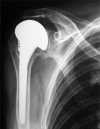

Use of cuff tear arthroplasty head prosthesis for rotator cuff arthropathy treatment in elderly patients with comorbidities

Objective: To evaluate the clinical and functional behavior of patients undergoing cuff tear arthroplasty at different stages of the disease.

Methods: Cuff tear arthroplasty hemiarthroplasties were performed in 34 patients with rotator cuff arthropathy and associated comorbidities, classified according to Seebauer. The mean age was 76.3 years, and the sample comprised 23 females (67.6%) and 11 males (32.4%). The mean follow-up period was 21.7 months, and evaluations were performed using the Visual Analog Scale for pain and the Constant scale.

Results: There were no statistically significant differences in the mean reduction in the Visual Analog Scale or in the Constant scale increase between the female and male groups. The variation between the pre- and postoperative Visual Analog Scale and Constant scale evaluations was significant. There was also no statistically significant difference between the Seebauer classification groups regarding the mean Visual Analog Scale reduction, or the mean Constant scale increase.

Conclusion: Cuff tear arthroplasty shoulder hemiarthroplasty is a good option for rotator cuff arthropathy in patients with comorbidities.